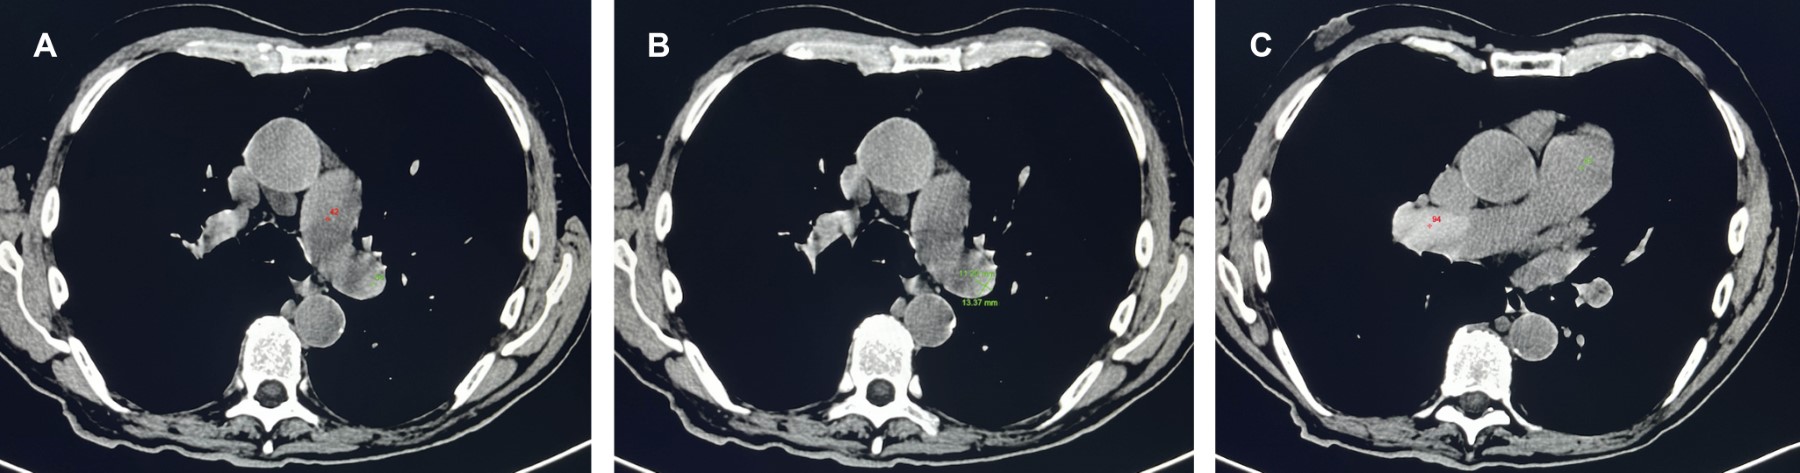

En algunos casos, la TC sin contraste puede mostrar émbolos densos en la arteria pulmonar, el signo intraluminal del defecto hiperdenso. Este signo es importante porque puede identificarse TEP en una TC simple, lo que ayuda a guiar imágenes adicionales para el inicio oportuno de la terapia adecuada (Figura 1).

Este signo tuvo una sensibilidad del 30% y una especificidad del 97.6% para detectar TEP agudo. La sensibilidad y especificidad del signo para detectar TEP central fueron del 57.1 y 97.6%, respectivamente, mientras que los porcentajes para detectar TEP periférica fueron del 8.2 y 97.6%, respectivamente.3 Por lo tanto, es un indicador útil de TEP agudo en TC de tórax simple, particularmente en casos que afectan a las arterias pulmonares centrales (Figura 2).4

Figura 1

Figura 2